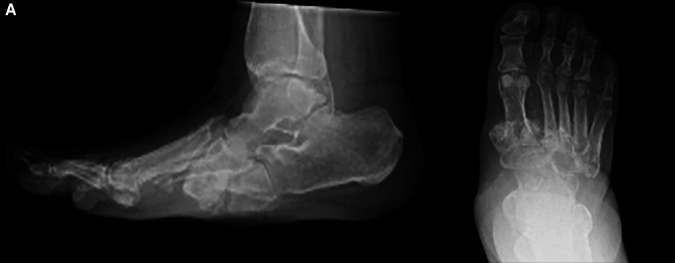

Charcot神经关节病累及足部是糖尿病的一种常见且潜在的破坏性并发症。除了良好的糖尿病控制,外科鞋和定期足部治疗,纠正足部畸形,防止溃疡,深部感染和肢体丧失,现在已经很好地建立了。血管功能不全在这组患者中很常见,传统的血管重建术并不总能成功治愈溃疡和治疗重症缺血。它会影响伤口和骨头的愈合。我们报告了在传统血运方法未能纠正严重缺血的情况下,成功使用改良的胫骨皮质横向运输技术(TTT)。我们已经用这种技术成功地治愈了软组织和骨骼。如何引用本文:Al Omar H, Lahoti O, Edmonds M,等。缺血Charcot中足重建联合胫骨外侧皮质横向转运1例。创伤肢体重建2025;20(1):50-55。

Charcot neuroarthropathy involving foot is a frequent and potentially a devastating complication of diabetes. In addition to good control of diabetes, surgical shoes and regular podiatric treatment, correction of foot deformity to prevent ulceration, deep infection and limb loss are now well established. Vascular insufficiency is common in this group of patients and traditional revascularisation procedures do not always succeed in healing ulcers and treating critical ischaemia. It compromises wound and bone healing. We report successful use of a modified technique of tibial cortex transverse transport (TTT) in a case where traditional revascularisation methods failed to correct critical ischaemia. We have achieved successful soft tissue and bone healing using this technique.